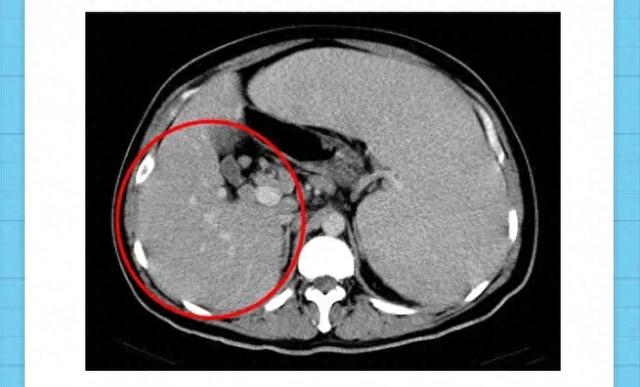

4、腹部CT或MRI:更清晰显示肝脏结构细节,鉴别病变性质,排查是否存在占位性病变,辅助诊断肝脏疾病。